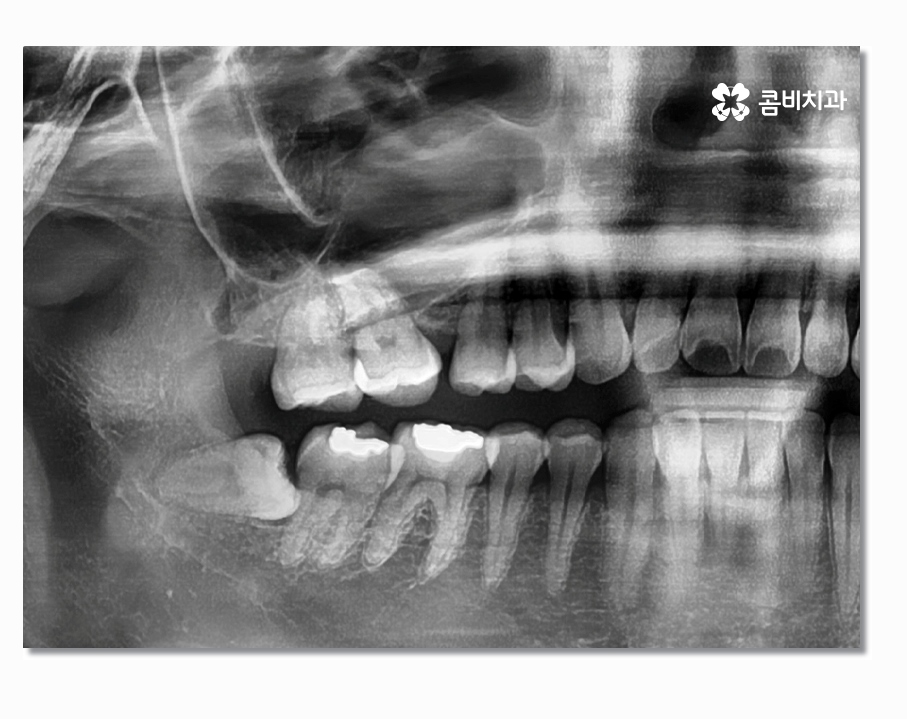

부분매복사랑니의 경우 치아가 반쯤만 잇몸 위에 맹출 되어 있어서

충치 및 잇몸질환을 일으키기도 하지만 누워서 자라는 형태인

경우도 많은데 이경우 어금니 사이에 충치를 발생시키거나

어금니를 녹게 만드는 경우도 있기 때문에 어금니 손상을 방지하기

위해서라도 발치를 서둘러야 하는 경우가 있어요

사랑니는 겉으로 보이는 것과 X Ray로 살펴보는 것이

큰 차이가 있으며 사랑니의 위치와 맹출 형태, 크기 등에 따라서

발치의 과정부터 시술 난이도의 차이가 있기 때문에